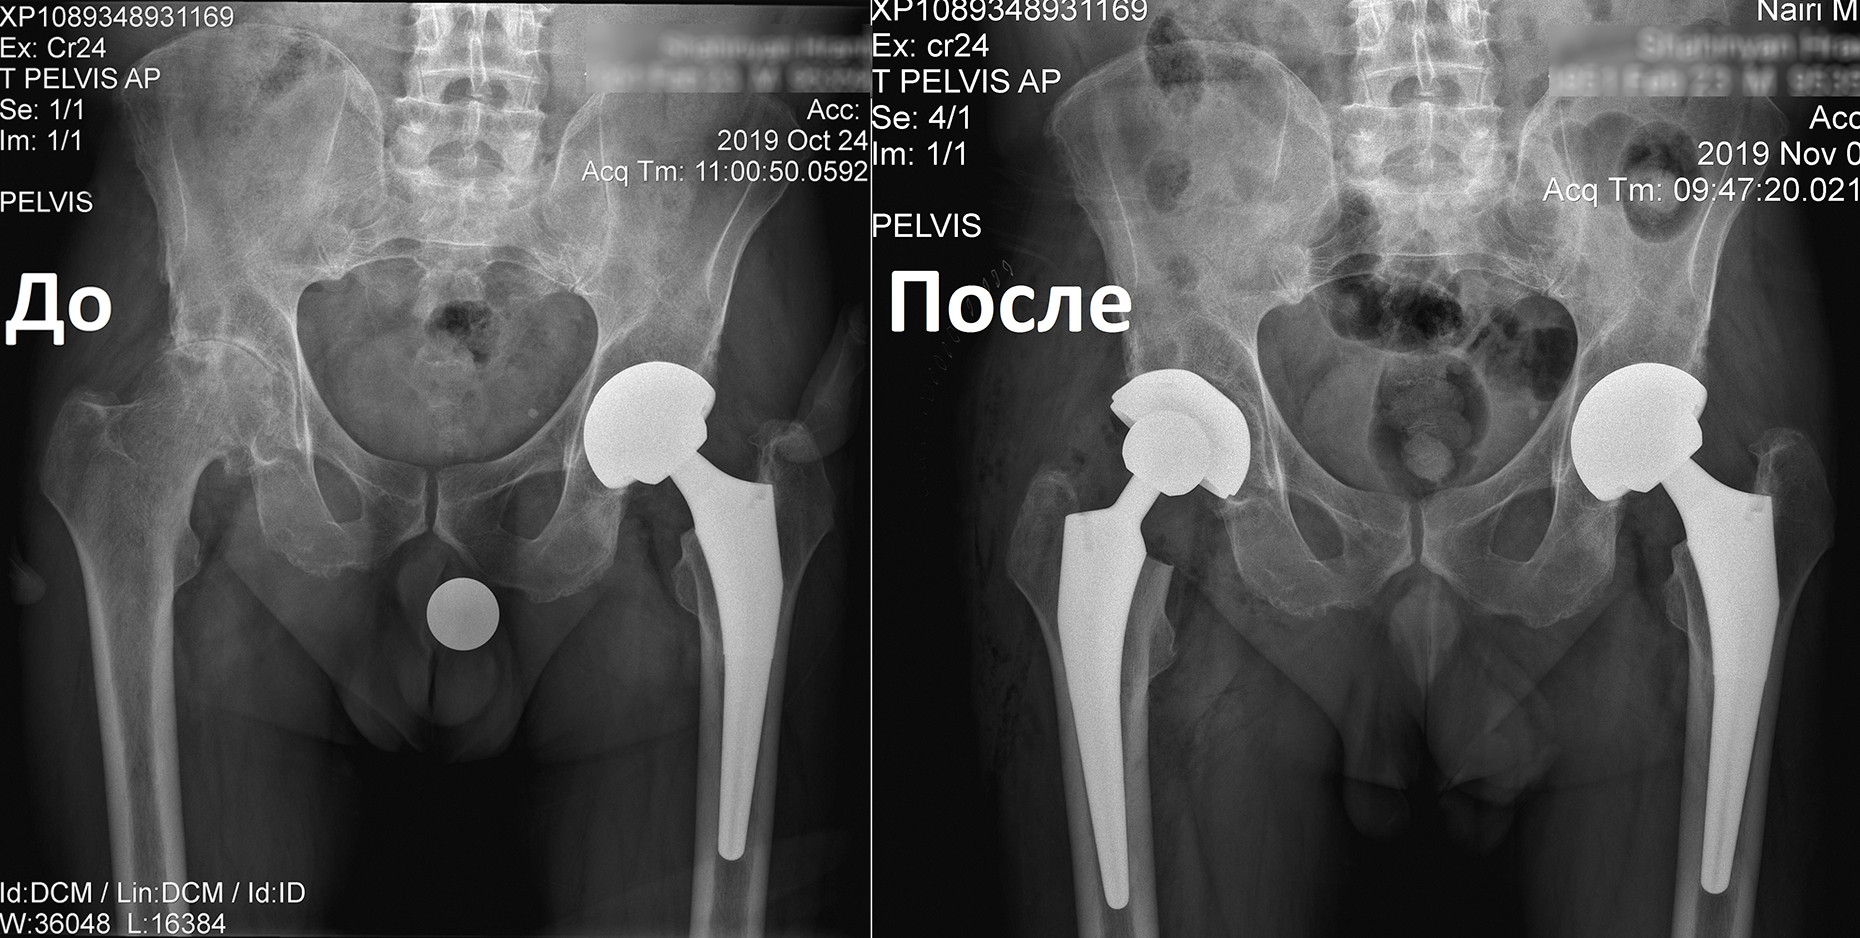

Կլինիկական դեպք. երկկողմանի անգիլիզացնող կոքսարթրոզ

«Նաիրի» բժշկական կենտրոն էր դիմել 1951 թ. ծնված տղամարդ՝ երկկողմանի անգիլիզացնող կոքսարթրոզով, առաջին աստիճանի ճարպակալումով: Պացիենտը գանգատվում էր մշտական ցավերից, շարժումների խիստ սահմանափակումից, քայլելու դժվարությունից՝ անգամ հենակների oգնությամբ:

Որոշում կայացվեց իրականացնել փուլային երկու վիրահատություն: Առաջինը վիրահատվեց ձախ ոտքը, քանի որ այդ վերջույթում ձևախախտումն առավել արտահայտված էր:

Երկու ամիս անց, երբ պացիենտը սկսեց քայլել առանց հենակների, վիրահատվեց նաև աջ ոտքը:

Երկրորդ վիրահատությունից 6 շաբաթ անց պացիենտը ցավեր չունի և քայլում է առանց հենակների, ապրում լիարժեք կյանքով: